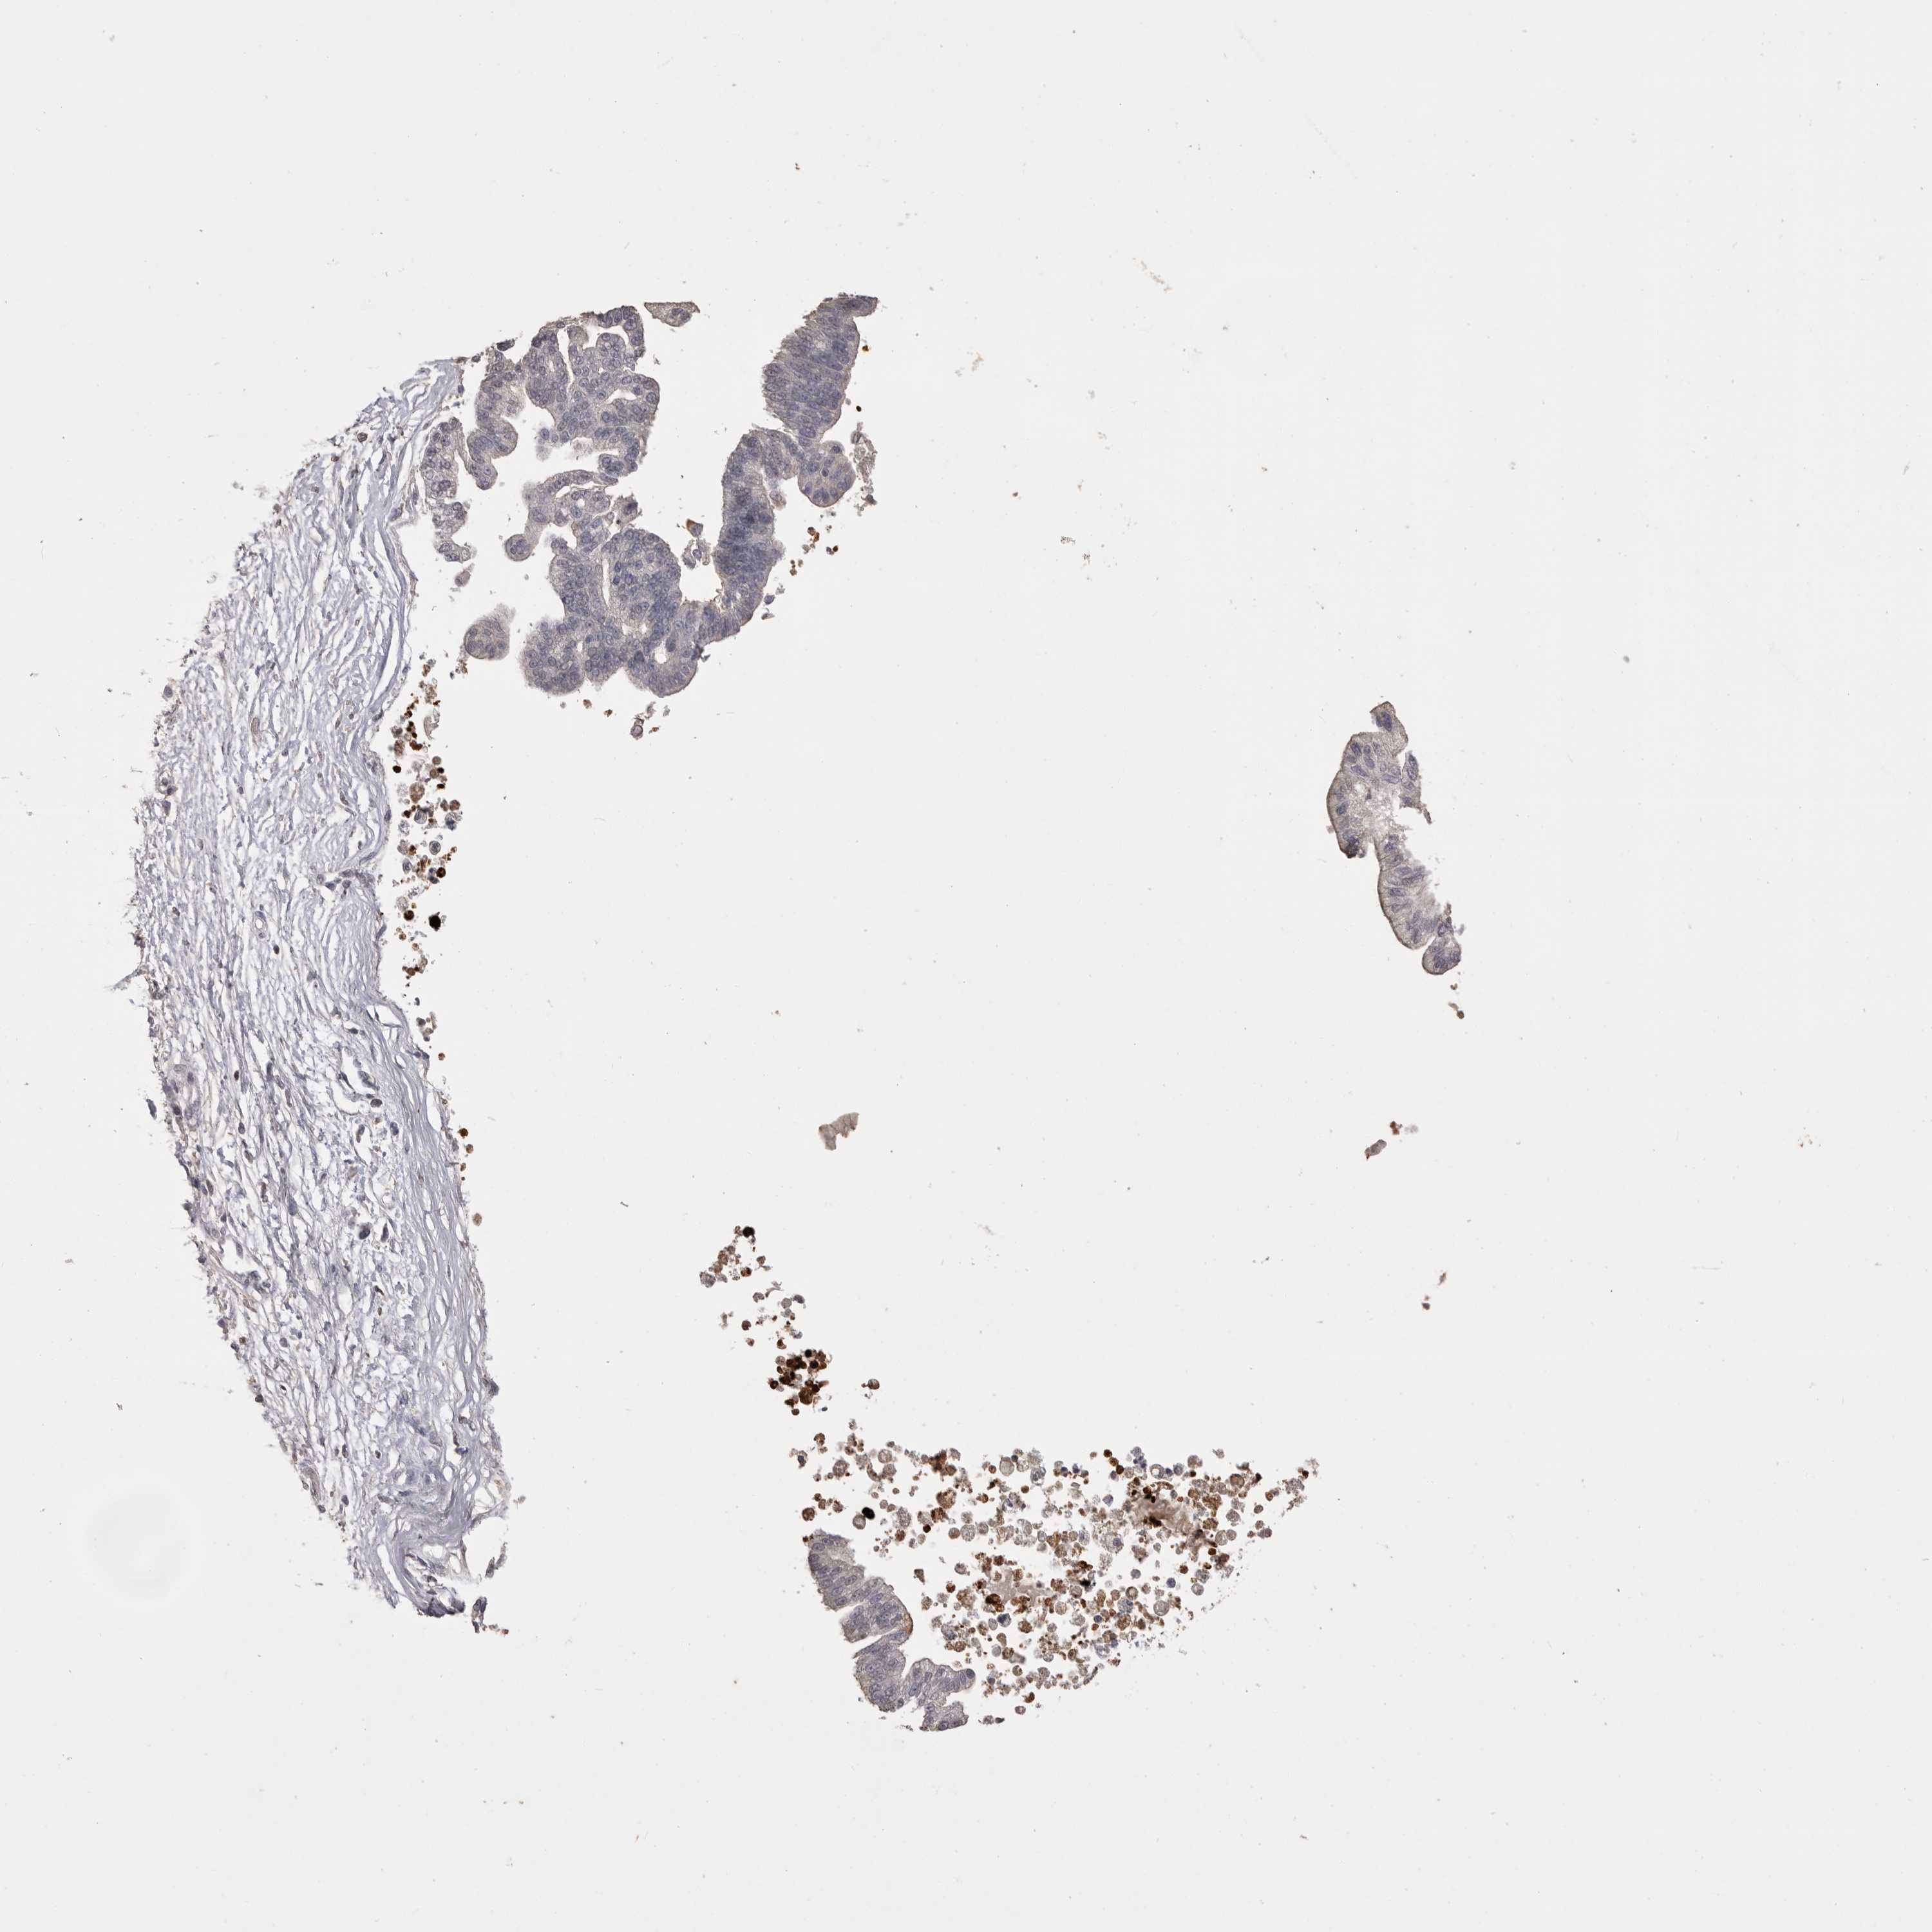

PANCREATIC CANCER - Protein expressioni

A mouse-over function shows sample information and annotation data. Click on an image to view it in a full screen mode. Samples can be filtered based on level of antibody staining by selecting one or several of the following categories: high, medium, low and not detected. The assay and annotation is described here.

Note that samples used for immunohistochemistry by the Human Protein Atlas do not correspond to samples in the TCGA dataset.

Antibody stainingi

Antibody staining in the annotated cell types in the current human tissue is reported as not detected, low, medium, or high, based on conventional immunohistochemistry profiling in selected tissues. This score is based on the combination of the staining intensity and fraction of stained cells.

Each image is clickable and will lead to virtual microscopy that enables deeper exploration of all samples and also displays staining intensity scores, fraction scores and subcellular localization as well as patient and tissue information for each sample.

Antibody CAB025869

Staining

High

Medium

Low

Not detected

Intensity

Strong

Moderate

Weak

Negative

Quantity

>75%

75%-25%

<25%

None

Location

Nuclear

Cytoplasmic/membranous

Cytoplasmic/membranous,nuclear

Adenocarcinoma, NOS